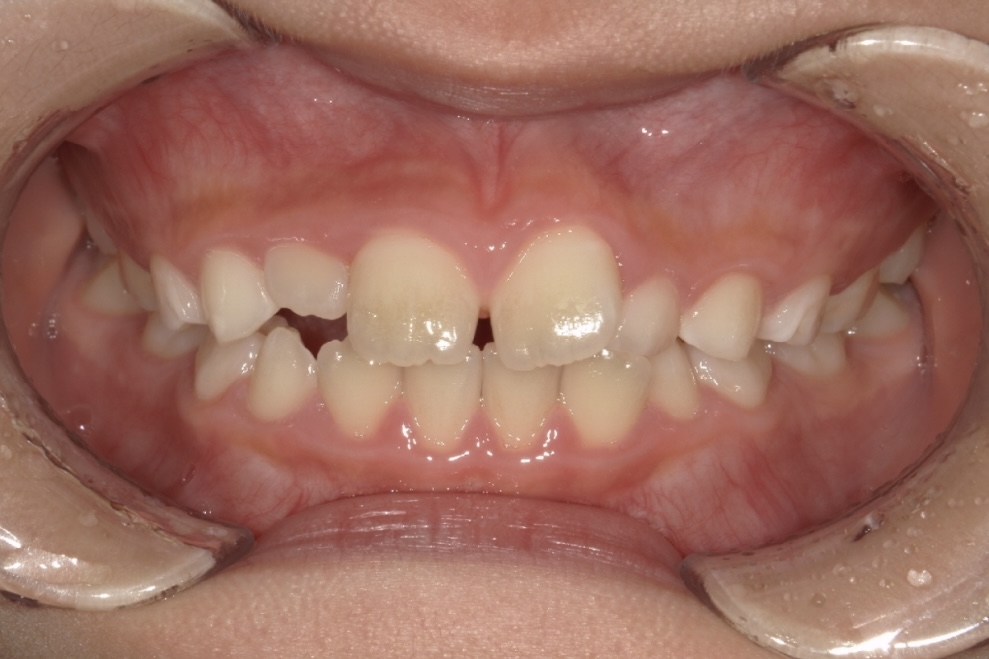

BEFORE

AFTER

9歳男児 すきっ歯とガタガタが気になる

主訴は歯並びのガタつきとすきっ歯でした。できるだけ痛みや不快感の少ない方法で治療を進めたいとのご希望をお持ちでした。

成長を活かした治療計画のもと、まずプレオルソを1年間使用し、歯列と顎のバランスを整えました。その後、マウスピース矯正インビザライン・ファーストにて矯正治療を行い、半年間で歯並びをさらに整えています。

段階的にアプローチすることで、無理なく歯列を改善し、見た目と機能の両面を整えることができた症例です。